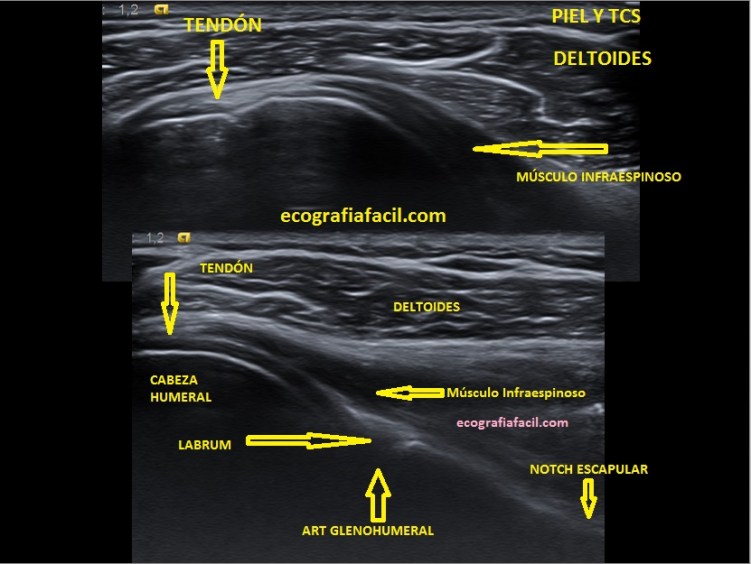

Tendón del Infraespinoso

Vamos a empezar Y TERMINAR ESTE PROTOCOLO DE HOMBRO, continuamos por el punto número 5. Tendón del Infraespinoso.

El estudio del tendón del Infraespinoso no es fácil, acceso complicado y estudio que requiere de destreza por la angulación y la colocación de la sonda y del propio paciente.

Colocación del paciente y Sonda:

- PACIENTE DANDO LA ESPALDA AL EXPLORADOR CON LA MANO DEL HOMBRO AFECTADO TOCANDO EL OTRO HOMBRO

- SONDA EN TRANSVERSO LIGERAMENTE INCLINADA

- ESTRUCTURAS:

- –TENDÓN INFRAESPINOSO

- –CABEZA HUMERAL

- –ARTICULACIÓN GLENOIDEA y LABRUM

- –NOTCH ESCAPULAR

- -DELTOIDES

Tocamos la espina escapular, cerca del húmero en el teórico lugar de la inserción del Infraespinoso y colocamos la sonda como os marco en la imagen, siempre debajo de la espina escapular, entonces tienes que buscar estas dos imágenes que te pongo a continuación juntas:

En la imagen ves dos imágenes, la de arriba es justo en la inserción, la de abajo es la imagen que tienes que conseguir para ver y estudiar el Labrum posterior, para eso deberás hacer un recorrido mínimo hacia la columna vertebral siguiendo el eje largo del músculo infraespinoso, sí, es dificil, me encantaría guiarte con la mano, pero de momento nos apañamos así.

Se complica la anatomía además…aparece el labrum y su función. También la Notch.

El tendón es afilado, muy afilado, hiperecogénico.

El Labrum posterior, pseudotriangular y también hiperecogénico.

La Notch escapular es una imagen en forma de bañera por donde pasa un paquete vasculonervioso que puede verse afectado por patología que comprometa dicha región y como resultado dé dolor locoregional. Esto pertenece a un estudio en un nivel 2.